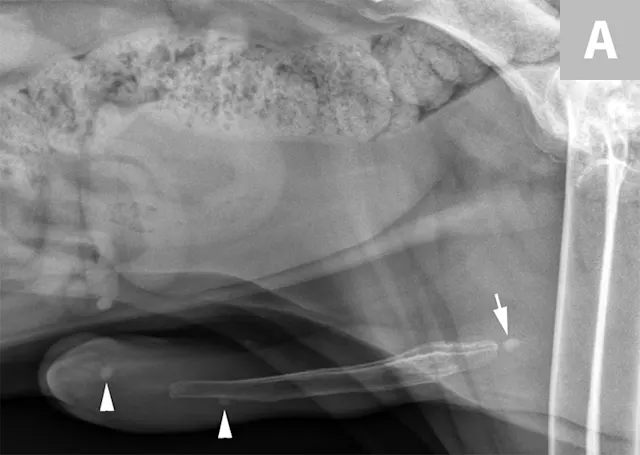

A separate center of ossification associated with the os penis may mimic a urethral calculus (Figure 11 A and B). A separate center of ossification can be seen at either end of the os penis and will be in line with the os penis. A calculus within the penile urethra would be seen ventral to the os penis in the location of the urethra. Contrast urethrography can be a helpful way to differentiate between a separate center of ossification and urethral calculus (Figure 11C).

FIGURE 11A

Lateral radiograph of a male dog collimated to include the urinary bladder and os penis. Note the well-defined mineral opacity just proximal to and at the same level as the base of the os penis—a separate center of ossification (arrow). Also note the two soft tissue opaque nodules summating with the prepuce, presumed to be small nipples (arrowheads).

Urinary bladder calculi can also descend into the urethra, which can potentially lead to urethral obstruction. In male dogs, it is imperative that the entire urethra is included within an additional radiographic image using the appropriate collimation (Figure 10).

Lateral x-ray of caudal aspect of dog with arrows pointing to radiopaque objects in penile urethra.

FIGURE 10

Lateral radiograph of a male dog centered on the perineum with the pelvic limbs pulled ventrally (flexion of the pelvis at the coxofemoral joints). This radiograph documents multiple well-defined, mineral opaque calculi within the penile urethra (arrows).